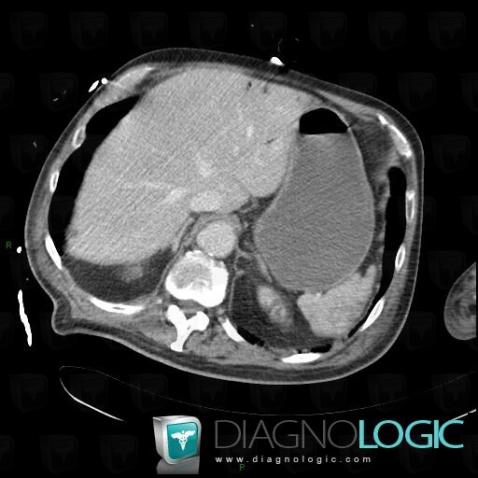

Portal venous gas, Liver, Portal vein and branches, CT

Here is the specific information in the key image above:

- Diagnosis Portal venous gas, Location(s) Portal vein and branches, with gamuts Liver, with gamuts